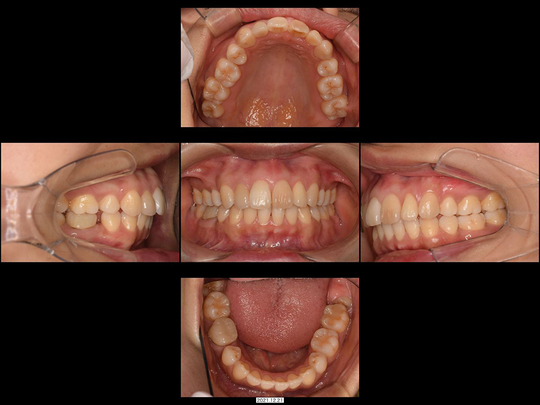

Kさん 20代前半 女性

矯正前

画像をクリックで拡大

矯正後

治療の説明

抜歯後、「入れ歯が嫌なら歯を削ってブリッジがインプラントにするしかない」と診断されたケースです。

精査の結果、CT画像上においても、インプラント治療は非常に困難で、ブリッジ治療を選択すると両サイドの歯の削る量が大きすぎるため、事前に神経を抜かないと対応が困難であることが判明しました。20代前半という年齢も考慮し、高齢者になってもメインテナンスしやすいのは、すべて自分の歯だけであることを考慮して、矯正治療を選択されました。表側の矯正装置にて上下の歯並び・咬み合わせを整えました。

治療の期間・回数

18か月、20回

​費用

985,600円